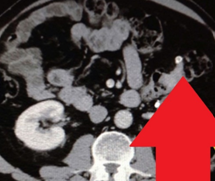

Εικόνες CT κοιλίας, που δείχνουν κυστικού τύπου βλάβη, μεταξύ ήπατος και ηπατικής καμπής του κόλου, σε επαφή με το εξωτερικό στρώμα του εντέρου, με πεπαχυσμένο τοίχωμα και χαμηλής πυκνότητας κέντρο (Ευγενική παραχώρηση Dr. V. Penopoulos)